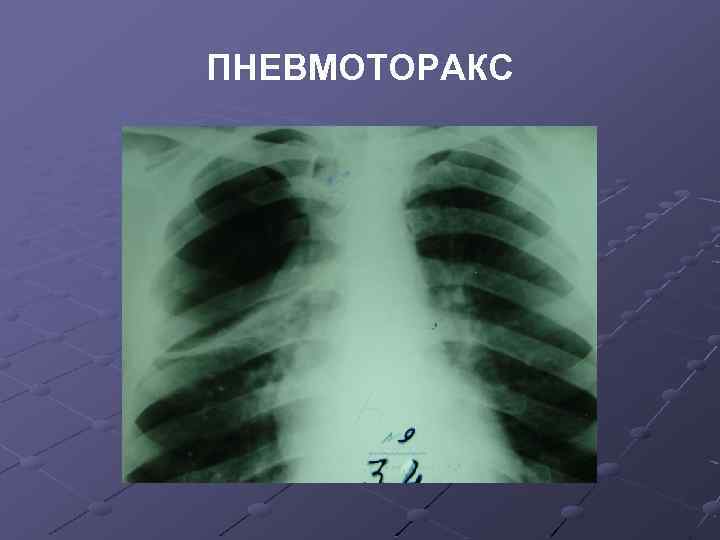

Рентгенологические изображения и синдромы патологии легких

Раздел: Кадры-подсказки